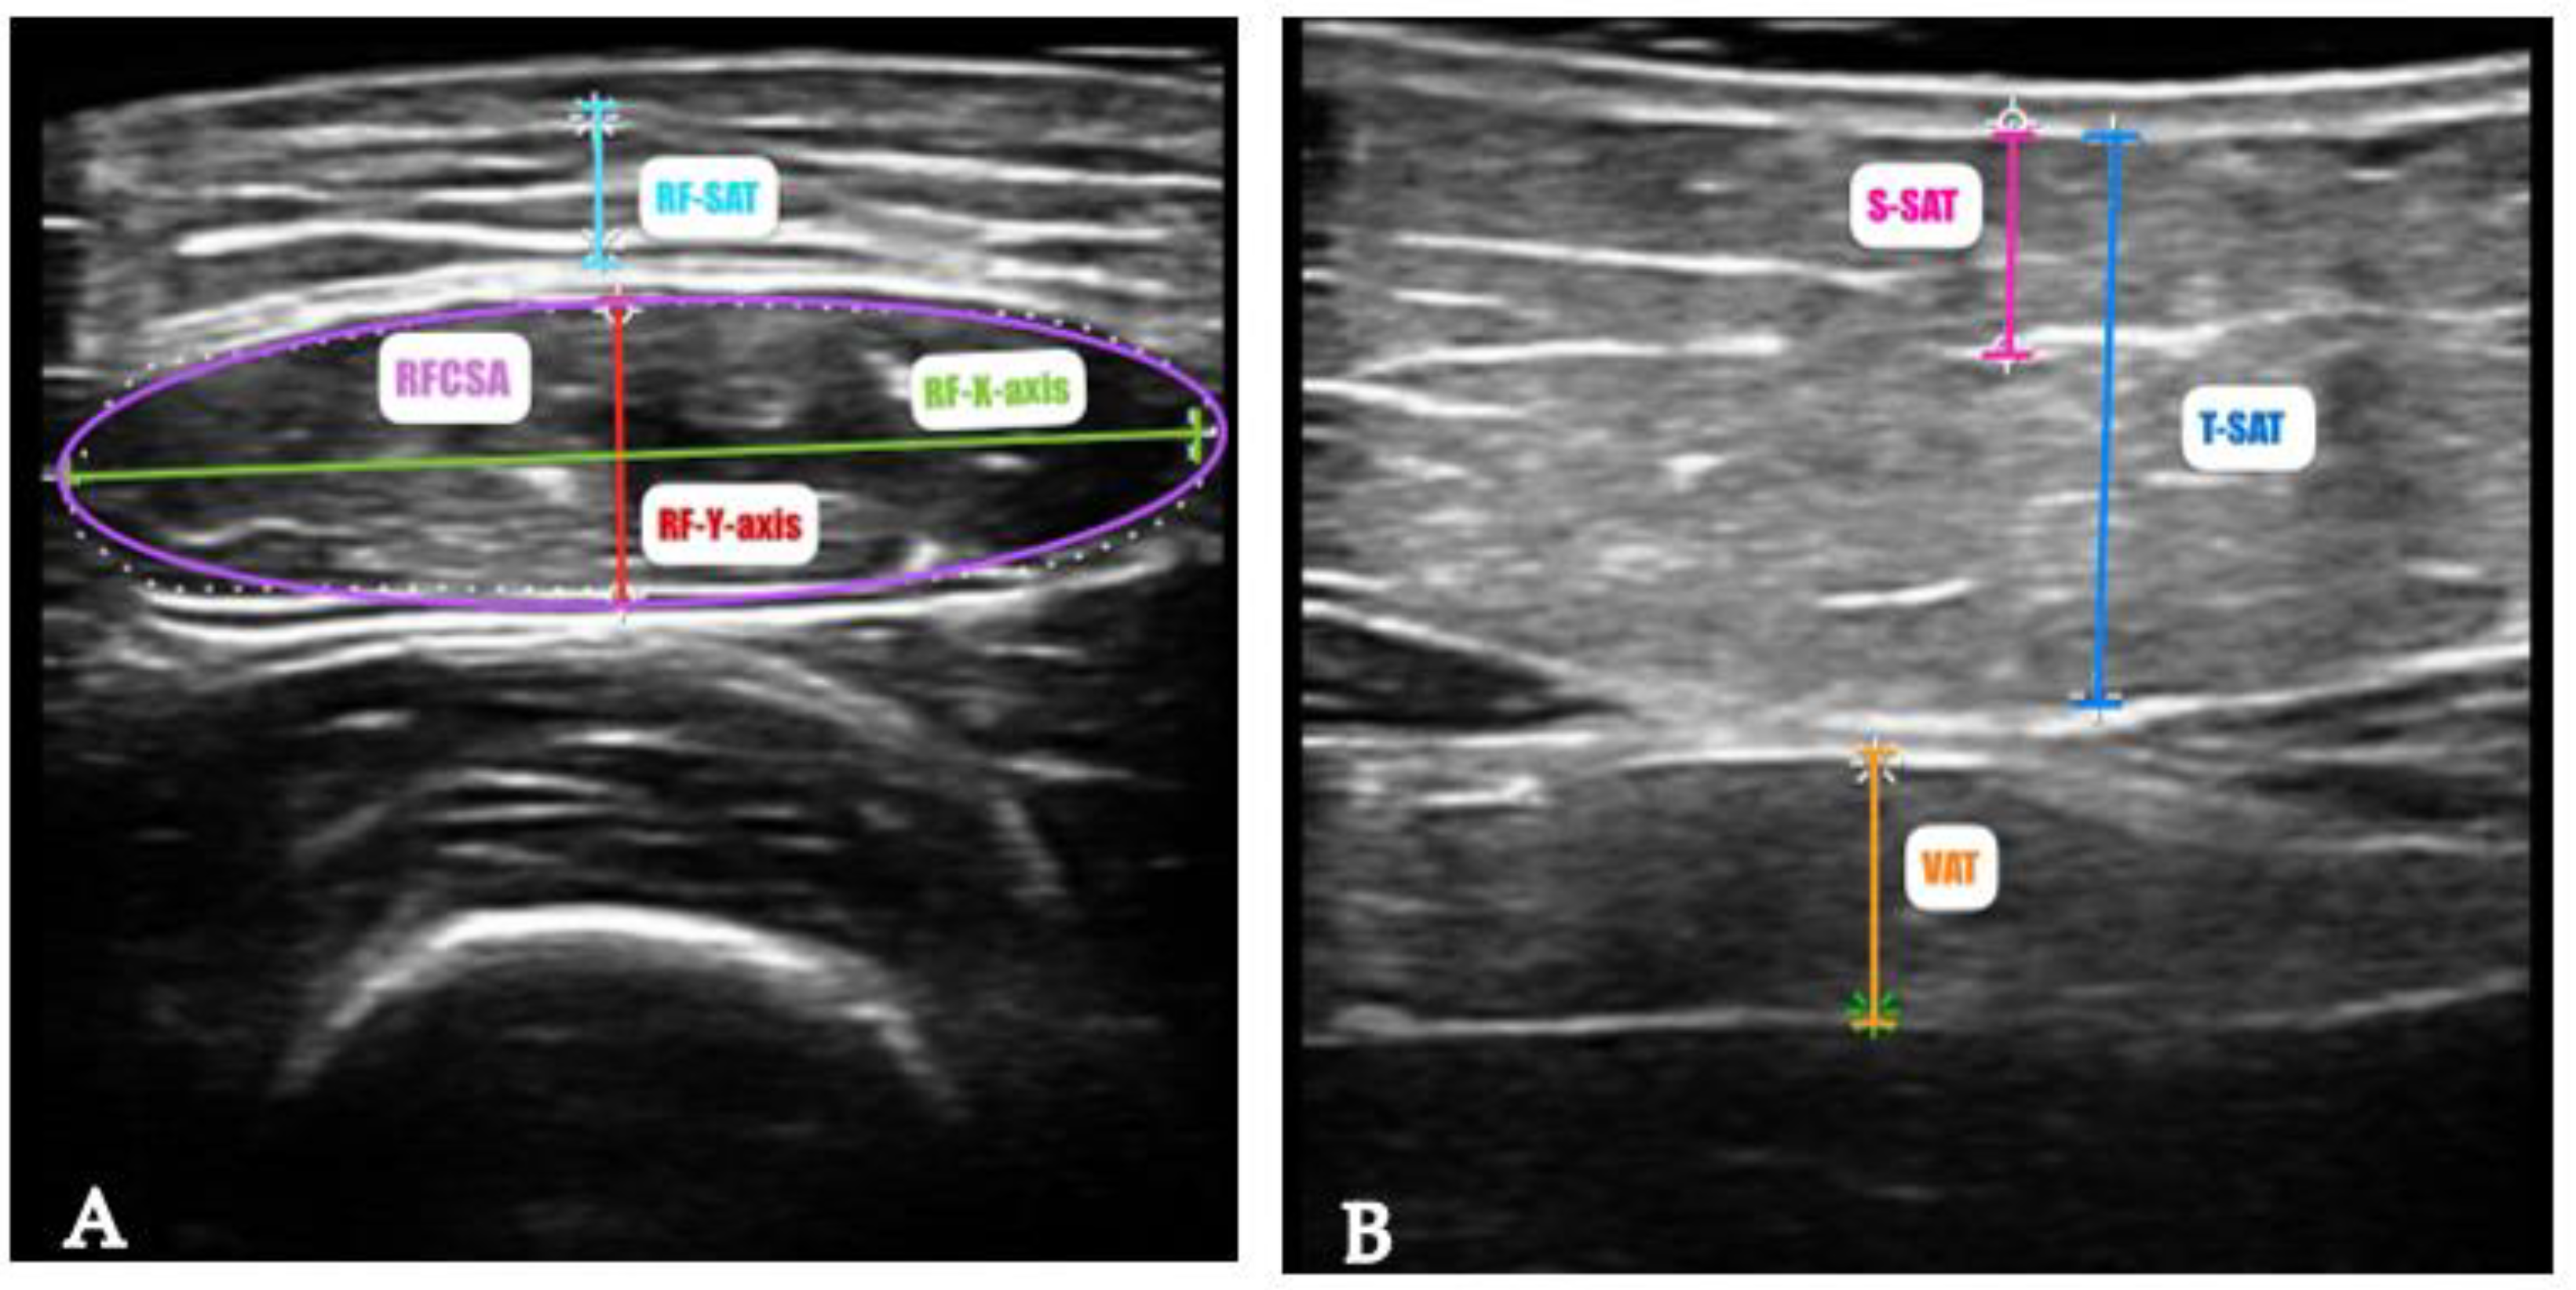

- García-Almeida, J.M.; García-García, C.; Vegas-Aguilar, I.M.; Ballesteros Pomar, M.D.; Cornejo-Pareja, I.M.; Fernández Medina, B.; de Luis Román, D.A.; Bellido Guerrero, D.; Bretón Lesmes, I.; Tinahones Madueño, F.J. Nutritional Ultrasound®: Conceptualisation, Technical Considerations and Standardisation. Endocrinol Diabetes Nutr 2023, 70, 74–84. [Google Scholar] [CrossRef]

| Nutritional ultrasound ®: rectus femoris muscle | |||

| RFCSA (cm2) | 2.8 ± 1.0 | 2.9 ± 1.02 | 2.2 ± 0.8 |

| RF-Y-axis (cm) | 0.8 ± 0.3 | 0.87 ± 0.27 | 0.77 ± 0.22 |

| RF-X-axis | 3.65 ± 0.50 | 3.76 ± 0.44 | 3.31 ± 0.55 |

| RF-AT (cm) | 0.41 (0.23 – 0.74) | 0.35 (0.24-0.55) | 0.78 (0.22-1.42) |

| Nutritional ultrasound ®: abdominal adipose tissue | |||

| T-SAT (cm | 1.4 (0.5-1.9) | 1.35 (0.47-1.85) | 1.41 (0.82-2.43) |

| S-SAT (cm) | 0.52 (0.28-0.87) | 0.47 (0.26-0.79) | 0.68 (0.35-1.06) |

| VAT (cm) | 0.55 (0.31-0.73) | 0.52 (0.30-0.65) | 0.58 (0.33-0.95) |